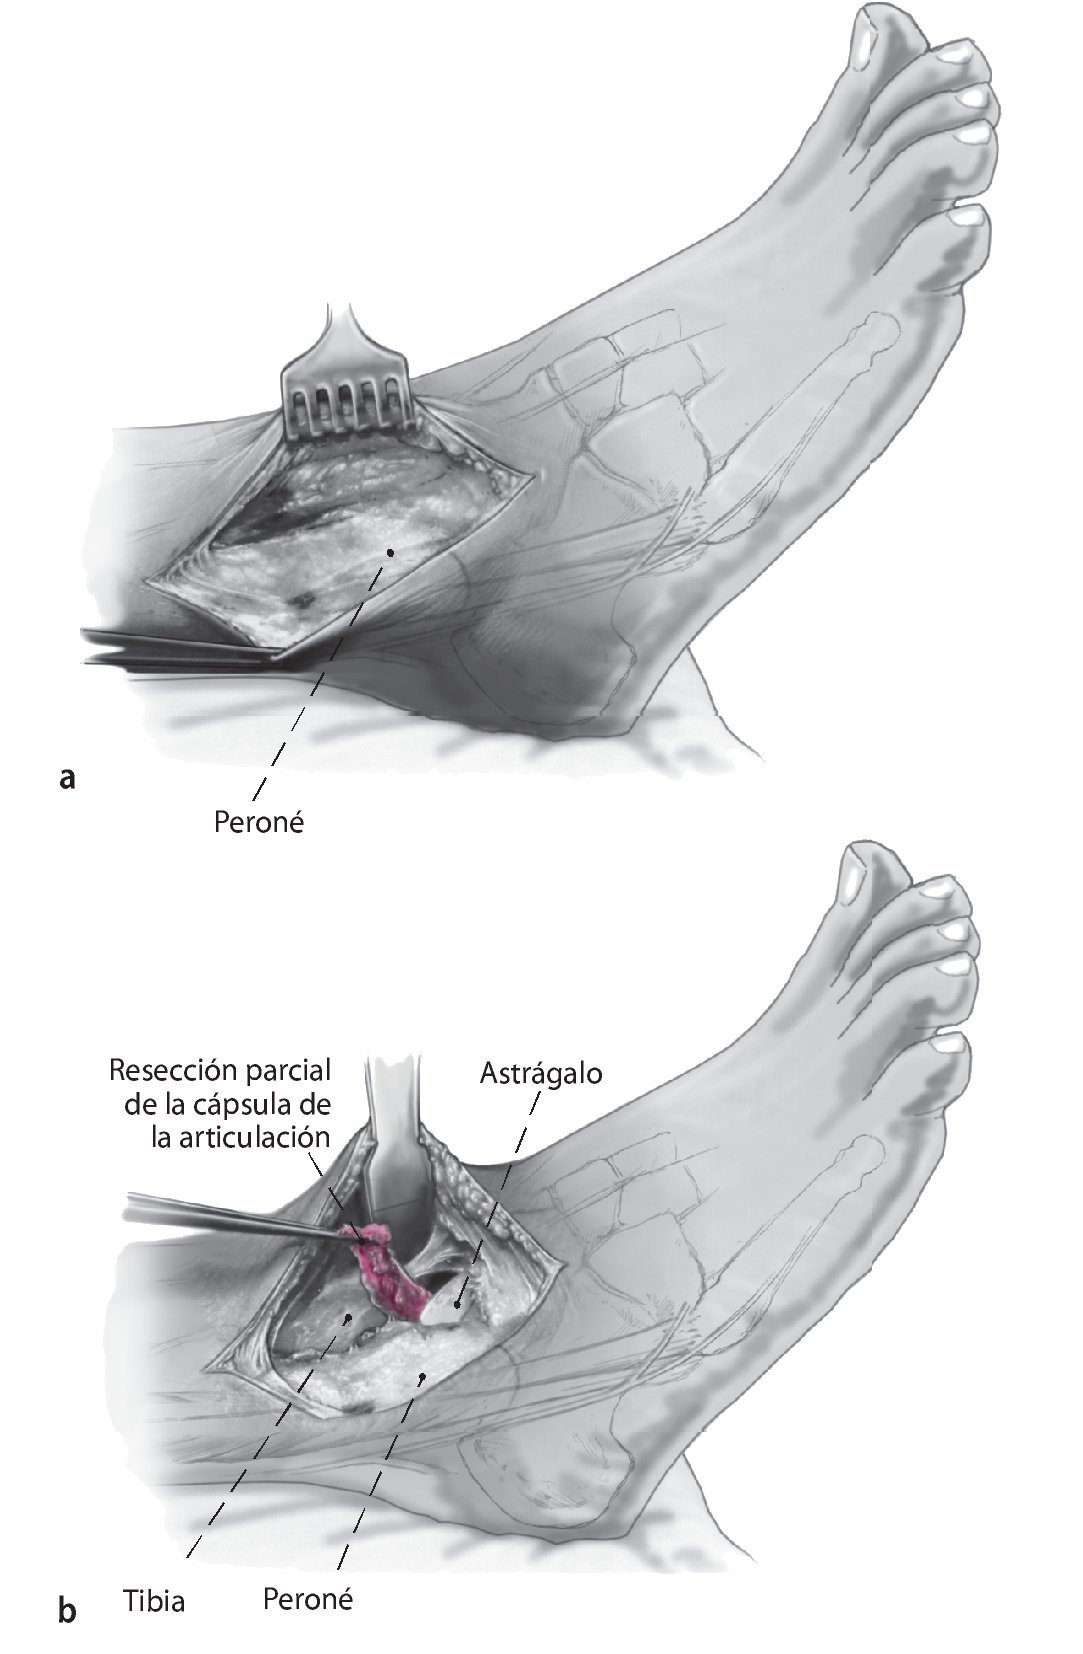

Fig. 1 Incisión lateral (a) y medial (b) . Ambas de 6-8 cm de longitud y el uso del maléolo lateral y medial como puntos de referencia.

Fig. 2 La incisión medial se lleva a cabo hasta el periostio (a). El daño a la vena safena mayor se evita mediante su retracción anterior. En el lado anteromedial, se reseca parcialmente la cápsula anterior (b). El retináculo extensor y los tejidos blandos se pueden mover como una capa para exponer la sección anteromedial de la articulación del tobillo. Se realiza incisión posterior del retináculo sobre el tendón tibial posterior para permitir la colocación protectora de un separador de Hohmann (b). La osteotomía del maléolo medial se realiza con sierra oscilante y se reseca la porción distal (c).

Fig. 3 Aborde el peroné desde un plano lateral en línea recta (a). La cápsula de la articulación se reseca parcialmente para dejar visible la sección tibioastragalina anterolateral (b). Realice una incisión en la vaina de tendón extensor y levante los tejidos blandos de la tibia en una sola capa. Ahora se puede colocar un separador de Hohmann para permitir una mejor visibilidad de toda la sección anterior del tobillo.